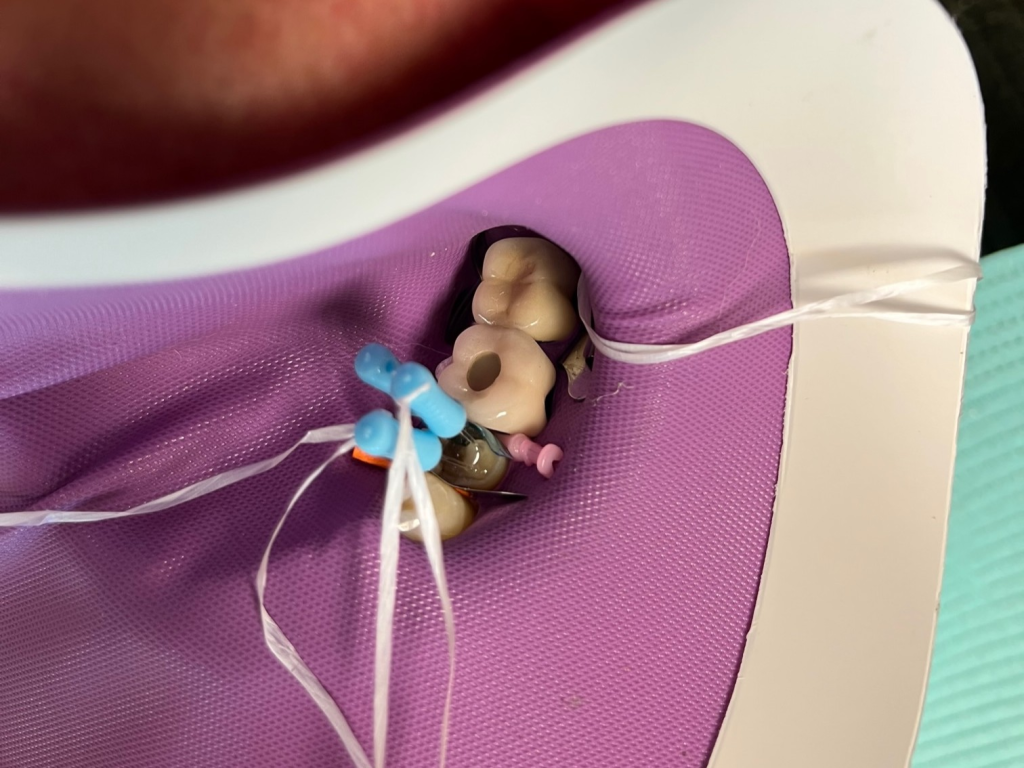

DentXpinTM repair.

6